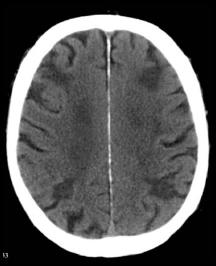

Infarcts due to hypoperfusion are generally located in the watershed areas between the major branches of the cerebral arteries. They occur in cases of prolonged ischemia. In such "low flow" states the areas at the farthest end of the circulatory system become hypoxic and, if the hypoxia is prolonged, undergo infarction. Heart failure, sepsis, and acute blood loss are common causes of watershed injuries to the brain.

When examining these CTs, remember that collections of blood will be radiodense. Initially infarcted brain will show minimal changes on a CT, but after a few days, there is marked effacement of the normal architecture.

Can you distinguish between these CTs and assign them each to one of the aforementioned categories?

Where would you expect hypoperfusion injury to occur? Click the question mark for a hint What other organ in the body is prone to hypoperfusion injury?